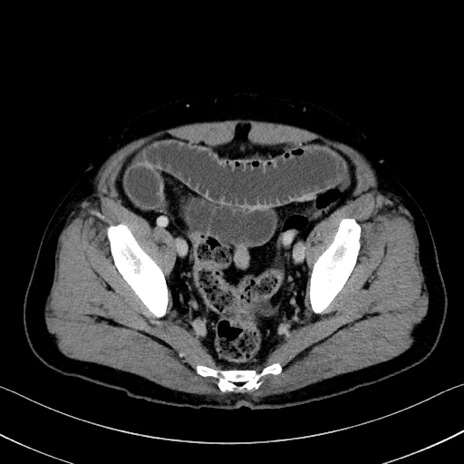

冠状断像

症例35(横断像)

【症例】70歳代 男性

【主訴】腹部膨満、嘔吐

【現病歴】昨日より腹部膨満感出現。本日増悪し、仙痛出現。嘔吐あり、受診。

【既往歴】糖尿病、胆摘後

【身体所見】BP 149/80mmHg、HR 74/min、BT 35.9℃、腹部:膨満、軟、圧痛なし。腸雑音減弱あり。上腹部正中切開瘢痕あり。

【データ】WBC 13500、CRP 1.72